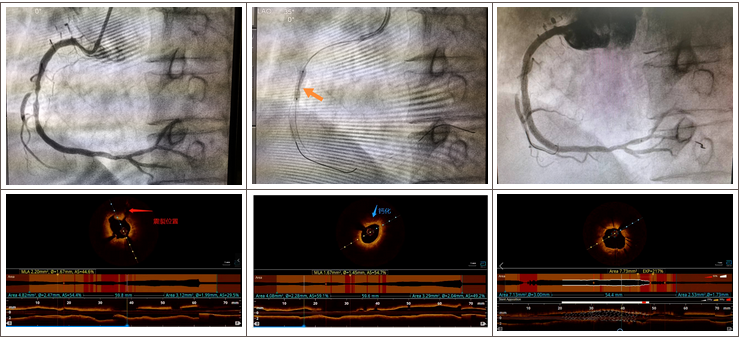

来到我院就诊后,张海山副教授应用shockwave IVL新技术为患者完成血管内冲击波碎石技术治疗。术中,张海山副教授首先使用2.5*15mm的预扩张球囊预扩,通过冠脉内光学相干成像(OCT)为患者进行影像学评估,发现患者右冠中段存在多处深层钙化病变,遂选择3.5*12mm的Shockwave IVL震波球囊对钙化病变处进行多个周期的冲击波治疗:松解钙化斑块、对治疗段进行低压球囊扩张成形、球囊泄压,恢复靶血管血流灌注。整个手术期间患者无明显不适,未见明显低血压、ST改变及持续性心律失常。冲击波治疗后复查造影可见右冠中段的钙化狭窄处明显改善,植入2枚药物支架并后扩效果满意,OCT提示支架贴壁和膨胀良好,术后患者胸闷症状明显好转。

治疗过程